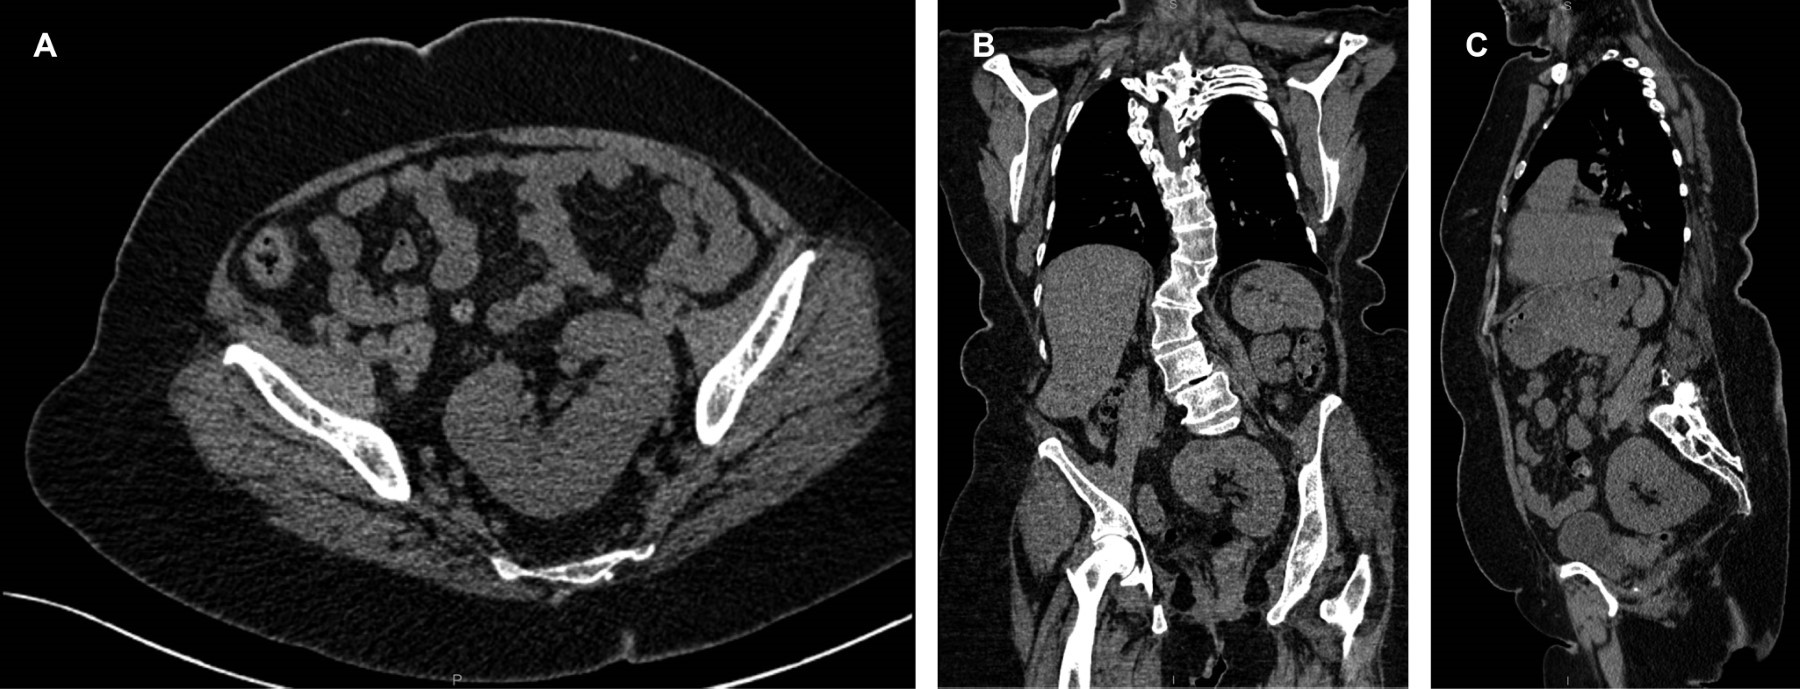

Paciente femenino de 54 años de edad, monorrena con síndrome de Turner y múltiples intervenciones quirúrgicas de columna dorsolumbar. Actualmente se encuentra en tratamiento con múltiples antiinflamatorios por artrosis de rodillas secundario a escoliosis. Se realizó estudio preoperatorio para evaluación de su columna con tomografía computarizada que en su evaluación abdominopélvica en fase simple y en reconstrucción multiplanar coronal y sagital (Figura 1) se delimitó hallazgo incidental de variante anatómica de tracto urinario del riñón izquierdo, caracterizada como en situación pélvica.

El hallazgo incidental de un riñón ectópico pélvico en una paciente con síndrome de Turner de 54 años refuerza la importancia de realizar una evaluación sistemática del aparato urinario, incluso en pacientes adultas y asintomáticas. La ectopia renal simple se origina cuando el riñón no completa su migración embrionaria hacia la fosa lumbar, permaneciendo en posición pélvica. Aunque generalmente es asintomática, esta condición puede asociarse con alteraciones funcionales, reflujo vesicoureteral, infecciones urinarias recurrentes o complicaciones durante procedimientos quirúrgicos y anestésicos.

En este caso, el diagnóstico fue fortuito, identificado mediante tomografía computarizada en un estudio preoperatorio de columna en una paciente con múltiples antecedentes quirúrgicos. Este hallazgo resalta el valor de la imagenología en la detección de anomalías renales congénitas, así como su papel en la planeación quirúrgica de pacientes con enfermedades sistémicas como el síndrome de Turner.

Figura 1